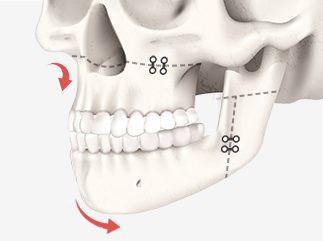

절골된 뼈를 단단히 고정해

움직이지 않도록 하여,

올바른 교합과 조화로운 얼굴로 완성합니다.

아래 턱뼈의 윗부분을 두 개의 핀으로 나누어

턱뼈를 이동시킨 후 겹쳐지게 하고,

고정핀을 이용하여 고정하는

일반적인 하악 수술법